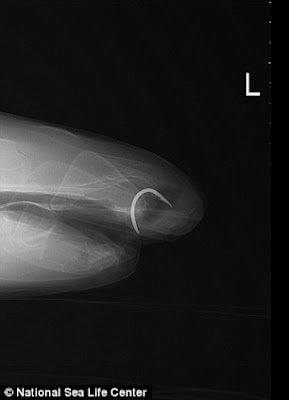

Florence, ikan yu sepanjang 6 kaki dari kumpulan Jerung Nurse, memulakan hidup sebagai seekor pemakan daging, tetapi selepas pembedahan pada tahun 2009 untuk membuang cangkuk berkarat dari rahangnya, ia telah berhenti makan ikan (daging) seperti biasa.

"Ia telah diberi imbasan ultrasound yang mendedahkan cangkuk pancing ikan yang tertanam jauh di dalam mulutnya."

Florence dibedah oleh pakar doktor haiwan Nick Masters dari Kumpulan Veterinar Zoo Antarabangsa di Bristol.

"Cangkuk itu dengan jelas telah berada di sana selama bertahun-tahun dan teruk berkarat dan ia telah membuatkan Florence sakit, " kata Graham.